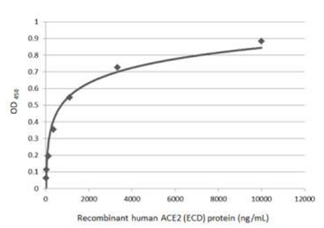

| Spike (S) | Spike full-length (~1273 a.a. in SARS-CoV-2) protein precursor is cleaved into glycosylated subunits, S1 and S2 (S2’). S1 binds to the host’s receptor, ACE2, while S2 mediates viral and host membrane fusion. | 1 |